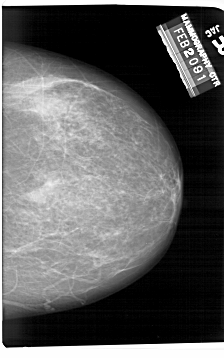

A_1407_1.RIGHT_CC

RIGHT_CC LINES 6796 PIXELS_PER_LINE 4246 BITS_PER_PIXEL 12 RESOLUTION 43.5 NON_OVERLAY